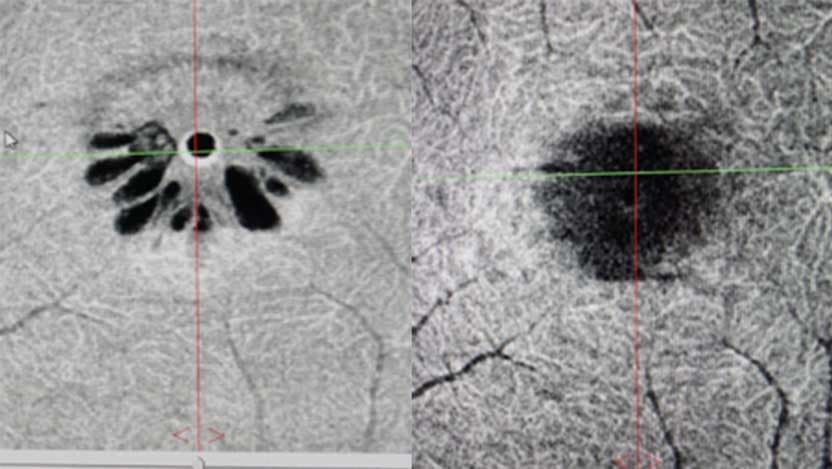

For Strickland, that was an easy choice. Her macular hole was small. There was some swelling around it as indicated by tiny cysts resembling the petals of a daisy. The hole had been there for at least three to four weeks probably longer, Skondra said. "Four days after we started the drops, the cysts were all gone and the hole was smaller.

Two weeks later, the hole had closed.